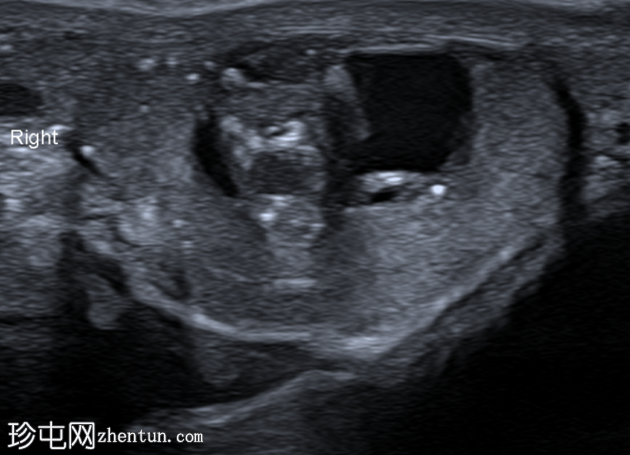

超声检查

纵切面

右侧睾丸内可见一异质性肿块,大小约10 x 14 x 15 mm,包含实性和囊性成分。肿块内可见多发小钙化灶。彩色多普勒超声检查显示肿块内血流信号较少。